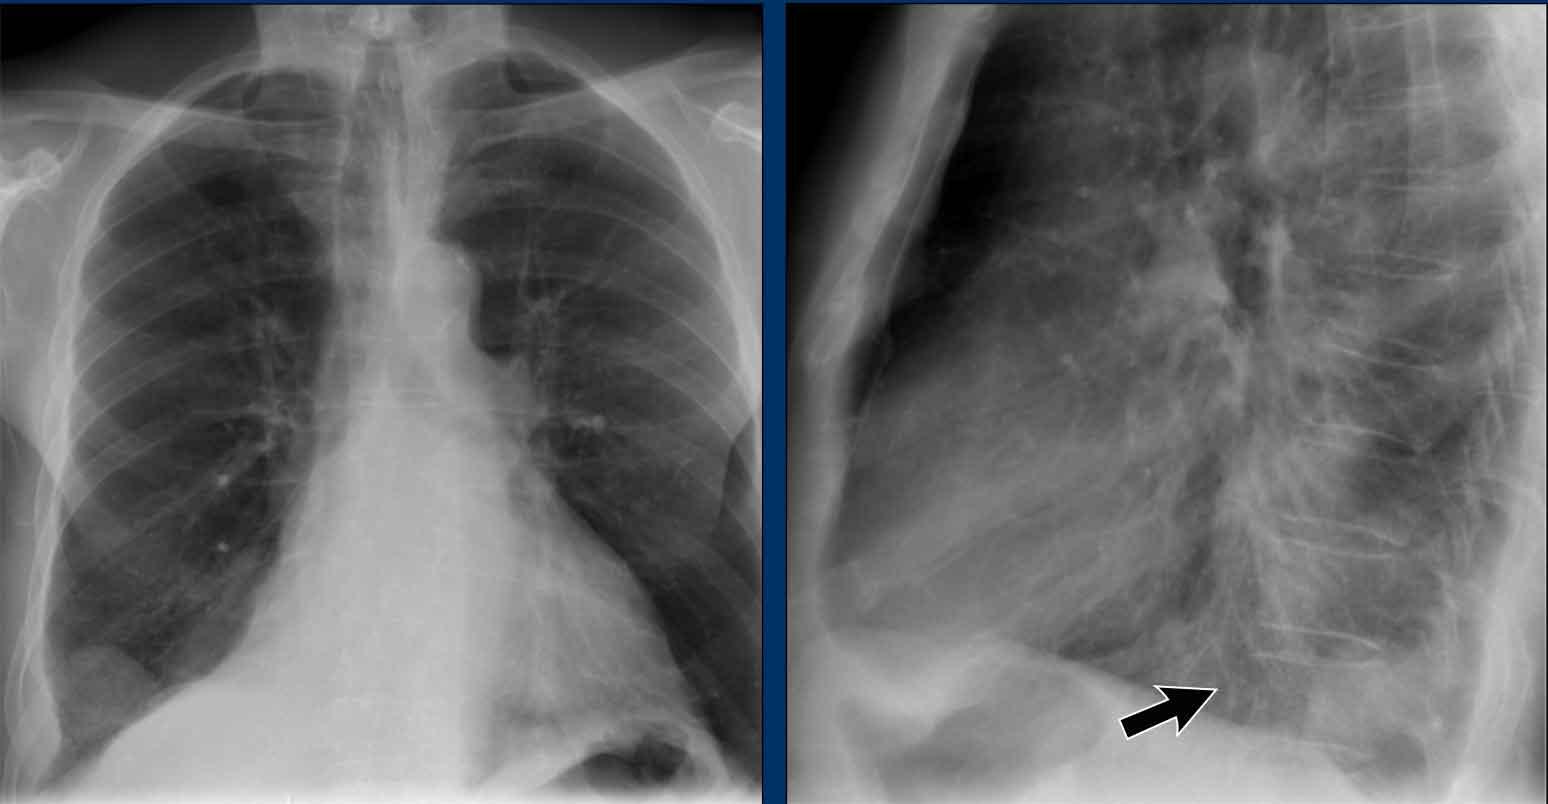

Trên phim X-quang ngực tư thế nghiêng, các bờ tim cần được xác định rõ ràng, và tĩnh mạch chủ dưới (IVC) thường có thể thấy đổ vào nhĩ phải.

Khoang sáng sau xương ức

Khoang sau xương ức bình thường chứa phổi có khí và do đó phải có hình ảnh thấu quang (tối trên phim), kéo dài xuống dưới đến mức thất phải tiếp xúc với xương ức (mũi tên đen nhỏ).

Bất kỳ hình mờ nào trong khoang sau xương ức phía trên đều đáng ngờ về tổn thương trung thất trước hoặc khối xuất phát từ các thùy trên của phổi.

Dấu hiệu cột sống

Khi đánh giá các thân đốt sống trên tư thế nghiêng, chúng phải có hình ảnh thấu quang (tối hơn) tăng dần từ trên xuống dưới do lượng phổi có khí chồng lên ngày càng nhiều (mũi tên trắng).

Nếu các đốt sống ngực dưới có hình ảnh đậm bất thường, điều này có thể gợi ý bệnh lý ở các thùy dưới, chẳng hạn như đông đặc hoặc khối — đây được gọi là dấu hiệu cột sống.

Đánh giá Cơ hoành

- Vòm hoành phải phải được nhìn thấy rõ ràng ở phía trước đến tận thành ngực (mũi tên đỏ), thể hiện ranh giới giữa phổi có khí và mô mềm ổ bụng.

- Vòm hoành trái thường chỉ nhìn thấy đến điểm tiếp giáp với bóng tim (mũi tên xanh lam), phía ngoài điểm đó ranh giới bị mất do tỷ trọng tương đương giữa tim và các tạng bụng phía trên.